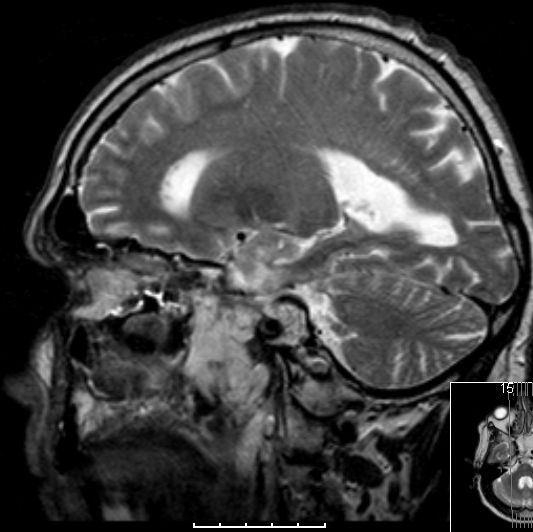

| Fall | Im vorliegenden Fall kam es während der Temodal-Therapie nach postoperativer Radiochemotherapie zu einen Durchbruch des GBs durch die Schädelbasis. | |